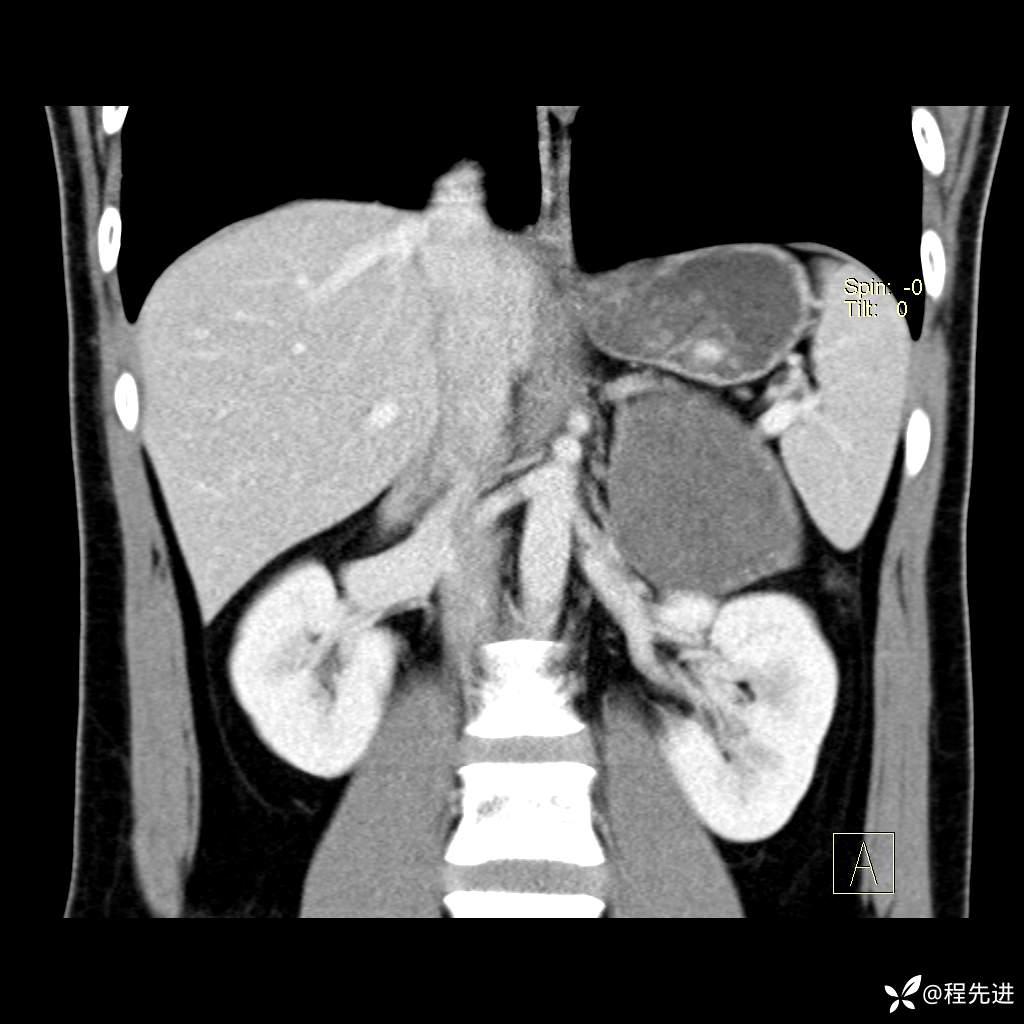

【腹盆】特别精彩病例|体检发现的左侧腹膜后占位期待您的精彩解读

患者年龄:25岁

简要病史:体检发现

CT平扫:(CT值:平扫,27HU,动脉期,27HU,门静脉期,31HU,平衡期,32HU)

冠状位重建: